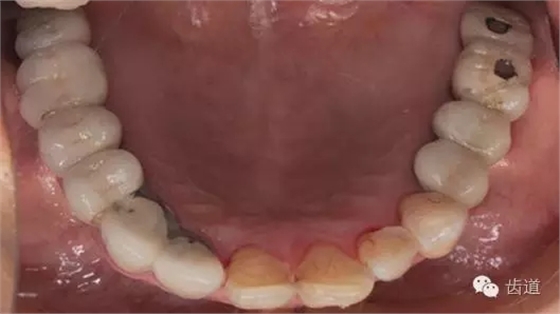

口內(nèi)檢查:

17-12,24-25烤瓷橋修復(fù),邊緣密合可,探-,叩-,松-。

35-38烤瓷橋修復(fù)體,邊緣密合欠佳,探針可探入,探-,叩-,松-。

17,16,26,27,36,37,47缺失。

46,45殘冠,部分白色充填物,繼發(fā)齲壞,探-,叩-,松-。

34遠(yuǎn)中鄰面深齲壞,探+,冷+,叩-,松-。

全口衛(wèi)生情況欠佳,可探及齦上及齦下牙結(jié)石,有牙齦探診出血,有牙齦退縮及牙周附著喪失。

3、下頜牙合面觀